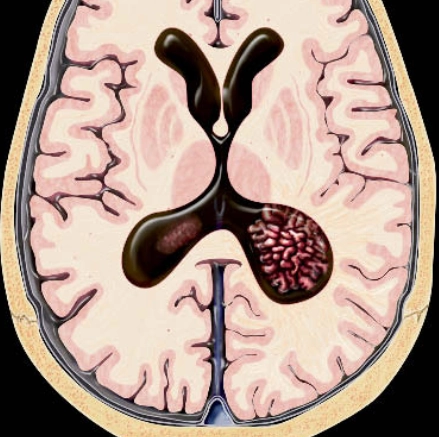

• U đám rối mạch mạc (Choroid Plexus Tumors)

• U nhú đám rối mạch mạc (Choroid Plexus Papilloma)